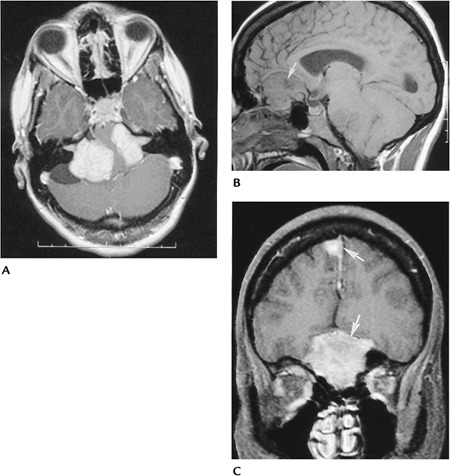

FIGURE 15-16 Neurofibromatosis Type 2. Bilateral vestibular nerve schwannomas and multiple meningiomas. (A)

Postcontrast axial MR image showing bilateral large vestibular nerve schwannomas extending into the internal auditory canals and compressing the pons. Sagittal (B) and coronal enhanced (C) T1-weighted images showing multiple meningiomas (arrows). |